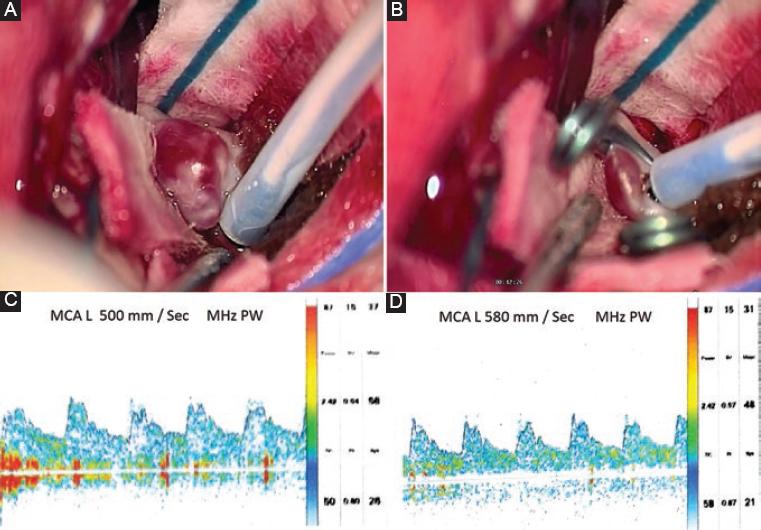

Mujer de 51 años, sin antecedentes médicos ni quirúrgicos, con historia de cefalea de 30 años de evolución que se presentaba de tres a cinco veces por mes, de tipo holocraneana, pulsátil, de moderada intensidad, que cedía con la ingesta de antiinflamatorios no esteroideos, sin alteraciones neurológicas asociadas. Incidentalmente, por el estudio de una masa en el cuello que se protocolizó con estudios de imagen, se evidenció un cortocircuito arteriovenoso parietoccipital medial izquierdo, por lo que es referida al servicio de neurocirugía, donde se le realiza angiografía diagnóstica y se encuentra una malformación arteriovenosa de 33 × 26 × 32 mm en la región parietooccipital izquierda, que recibía suministro sanguíneo a través de las arterias cerebral media izquierda y cerebral posterior homolateral, con drenaje venoso superficial hacia el seno sagital superior y el seno transverso, clasificándose como de grado III en la escala de Spetzler-Martin, con aneurismas proximales de 3.1 × 2 × 3.3 mm en el segmento M1 y de 5.7 × 6.2 × 7 mm en la bifurcación de la arteria cerebral media izquierda. Se plantea como manejo inicial la embolización de los aneurismas proximales con material cohesivo, pero durante la intervención endovascular se observa una compresión de la arteria temporal posterior, por lo cual se decide retirar el material cohesivo y dar por concluido el procedimiento de manera incompleta. Posteriormente se plantea embolizar la malformación arteriovenosa a través de la arteria occipital izquierda, logrando una embolización del 90% (Fig. 1), y en un segundo tiempo quirúrgico se realiza el clipaje del aneurisma de mayor tamaño, a través de un abordaje pterional izquierdo, monitorizando con Doppler transcraneal las velocidades de flujo sanguíneo durante todo el procedimiento (Fig. 2). Finalmente se concluye sin complicaciones y la evolución en su recuperación es adecuada. A los 6 meses se realiza una craneotomía para la resección completa de las malformaciones arteriovenosas cerebrales, que concluye sin complicaciones, con sangrado mínimo y adecuada recuperación neurológica (Fig. 3).

Figura 2 A-B: fotografías del clipaje del aneurisma de mayor tamaño en la bifurcación de la arteria cerebral media izquierda a través de una ventana pterional con monitorización Doppler. C-D: controles de velocidades de flujo antes y después del clipaje del aneurisma con Doppler transcraneal.

La utilización del Doppler transcraneal en el clipaje de aneurismas tiene el beneficio de ser no invasivo y de monitorizar en tiempo real los cambios hemodinámicos, previniendo y permitiendo tratar de manera oportuna el vasoespasmo cerebral cuando se llega a presentar. Tiene una sensibilidad del 83% y una especificidad del 88%, y es de mayor utilidad en el clipaje de aneurismas que en su tratamiento endovascular. Se ha descrito que velocidades de flujo de 120-140 cm/s, 140-200 cm/s y > 200 cm/s en la arteria cerebral media18, que es donde se ubicaba el transductor utilizado en nuestro caso, son concordantes con vasoespasmo leve, moderado y grave, respectivamente. Durante nuestro procedimiento se mantuvo en 50-58 cm/s antes, durante y posterior al clipaje.